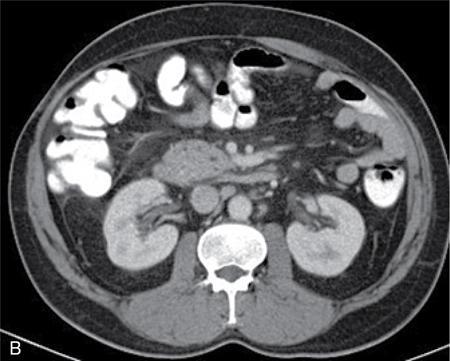

Amit Kumar Kamble, Abhinav Ranwaka The adult urinary system is formed of a pair of kidneys, a pair of ureters, a urinary bladder and a urethra. All these structures are extraperitoneal in location and extend from upper abdomen to the pelvis and into the exterior. These organs can be visualised on a host of imaging modalities, and a knowledge of these appearances helps the radiologist identify the relevant pathologies. Having a complex embryological development, the urinary system can have a wide spectrum of normal and abnormal anatomical variants. This chapter describes the appearance of the urinary system in commonly used imaging modalities and their common variants. Kidneys are paired bean-shaped structures situated in the retroperitoneum on either side of the vertebral column. The kidney consists of The renal sinus contains: The kidneys are surrounded by the renal capsule which is enclosed in the perirenal space. This space predominantly contains the perinephric fat and has thin septations within (Kunin’s septa); these septae may be thickened in various renal pathologies seen as perinephric stranding on imaging. The perirenal space is bounded by the perirenal fasciae, called the Gerota fascia (anterior perirenal fascia) and Zuckerkandl fascia (posterior perirenal fascia). The leaves of perirenal fascia fuse superiorly, laterally and medially. Superiorly, the perirenal fasciae also enclose the adrenal gland, which is separated from the kidney by a septum (Fig. 10.2.2). The anterior and posterior perirenal fasciae fuse laterally to form the lateral conal fascia. Medially, the perirenal fascia also encloses the renal pedicle. Medially, it communicates with renal sinus fat. There may be the communication of perirenal spaces across the midline. Superiorly, the perirenal space communicates with the bare area of the liver or spleen. The ureter arises from the perirenal space and travels inferiorly in anterior pararenal space. Inferiorly, the perinephric space may communicate with periureteric tissues. Interfascial planes are potential planes in between the leaves of the anterior perirenal fascia, called the retromesenteric plane and in the anterior perirenal fascia called the retrorenal plane. Anterior pararenal space: It is bounded by parietal peritoneum anteriorly, anterior perirenal fascia (Gerota) posteriorly and lateral conal fascia laterally. The anterior pararenal space contains the pancreas, second and third part of the duodenum, the retroperitoneal segments of ascending and descending colon and the roots of the small bowel mesentery and transverse mesocolon. Posterior pararenal space: It is bounded by posterior perirenal fascia (Zuckerkandl) anteriorly, fascia transversalis posteriorly and lateral conal fascia laterally. Caudally, the pararenal spaces communicate with each other and also with the extraperitoneal spaces. All the three spaces communicate at the pelvic brim. Understanding of the anatomy of spaces around the kidney is important for local staging of renal pathologies. Renal arteries are the branches of abdominal aorta. They originate laterally from the aorta below the origin of superior mesenteric artery. Accessory unilateral renal artery occurs in 30% of the population and bilaterally in 10% of population. Renal artery is divided into anterior division, which divides into four segmental branches and a posterior division; these arteries are end arteries supplying the respective segments of the kidneys (Fig. 10.2.3): apical, upper, middle, lower segments supplied by the anterior division, and a posterior segment supplied by the posterior division. The segmental arteries divide into lobar branches one to each to renal pyramid. Before reaching to pyramid, they divide into two to three interlobar branches. At the junction of cortex and medulla, interlobar arteries divide into arcuate arteries at the right angle. They further subdivide into interlobular artery, afferent and efferent arterioles. The efferent arteriole drains into peritubular plexus. The plane where the branches of the anterior and posterior divisions meet is located between the anterior two-thirds and posterior one-third of the kidney and is relatively avascular; it is called the avascular plane of Brodel (Fig. 10.2.3), and is a relatively safe site for nephrostomy access. Peritubular plexus converges to form the interlobular vein. These veins accompany their arterial counterparts and drain into the renal vein. The renal veins are situated anteriorly to the renal arteries and finally drain into the inferior vena cava at the right angles (Fig. 10.2.4). The two left renal veins may be present one passing anterior and other posterior to the aorta known as persistence of renal collar. Sometimes a single retroaortic left renal vein (Fig. 10.2.5) may be present. Supernumerary right renal vein may be seen. Renal vein variations are more common on the right side. The lymphatics of the kidneys drain into the lateral aortic nodes at the level of origin of renal arteries. Normal kidneys may be visualised on a frontal abdominal radiograph as faint oval shadows on either side of the vertebral column immediately besides the psoas shadows (Fig. 10.2.6). On contrast radiography and intravenous urography, the renal shadows show gradual opacification, peaking between 30 and 60 seconds followed by opacification of the pelvicalyceal system on subsequent radiographs. The kidneys are visualised in longitudinal and transverse views usually by placing the probe in the loin with the patient in supine or lateral position. The normal kidneys appear less echogenic than the liver and show a thin echogenic capsule. The surface of the kidney is usually smooth in adults, and may be lobulated in infants and young children. The renal parenchyma shows an outer cortex, which generally shows a uniform thickness, surrounding the less echogenic medullary pyramids, with invaginations of the columns of Bertin between the medullary pyramids (Fig. 10.2.7). This differentiation between the echogenicity of the cortex and medulla is called corticomedullary differentiation, which is lost in certain disease states. The renal pyramids are most hypoechoic compared in infancy gradually becoming less hypoechoic with age. The hypoechoic renal pyramids may at times be confused for hydronephrosis by an inexperienced observer. Arcuate arteries may be identified in some adults between the cortex and medulla as linear echogenic lines (Fig. 10.2.8A) and should not be mistaken for calculi. The renal sinus is seen as a central hyperechoic area of the kidneys owing to the presence of fat. The renal calyces and pelvis are not visualised normally as they are collapsed. They may sometimes be seen if the bladder is overdistended, a finding which reverses once the patient emptied the bladder. Doppler interrogation allows evaluation of the renal vasculature in great detail. The renal artery, its segmental, interlobular and arcuate branches and the corresponding veins can be easily visualised (Fig. 10.2.8B). At the renal hilum, the renal vein lies anterior to the renal artery. The right renal artery is longer and lies posterior to the inferior vena cava (IVC). The left renal vein crosses midline and courses in between the aorta and superior mesenteric artery. On CT scan (Fig. 10.2.9), the kidneys are well identified and well demarcated owing to the presence of surrounding fat. They show a homogeneous appearance with intermediate density between 35 and 55 HU on non-contrast CT scan with a central low-density renal sinus.